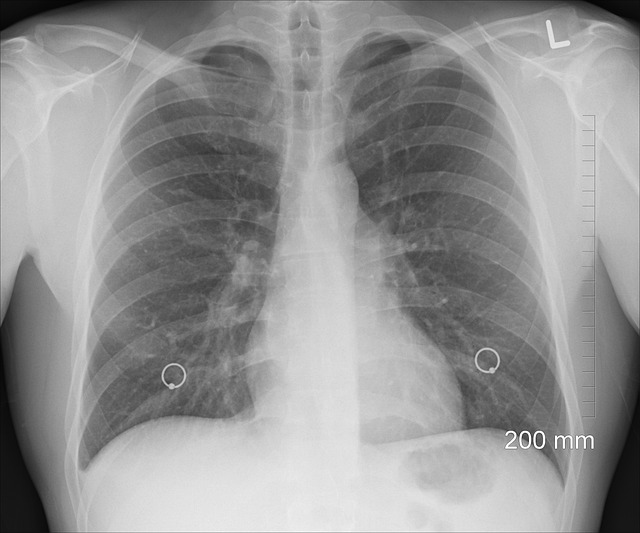

๋ณ๊ธฐ๋ณ ์ง๋จ๊ณผ ์์ ์ฌ๋ถ

๋น์์ธํฌ์ฑ ํ์์ ๋ณ๊ธฐ์ ๋ฐ๋ผ ์น๋ฃ ๋ฐฉ๋ฒ๊ณผ ์์กด์จ์ด ๊ทน๋ช ํ๊ฒ ๋๋ฉ๋๋ค. ๋ณ๊ธฐ๋ ์ผ๋ฐ์ ์ผ๋ก 1๊ธฐ๋ถํฐ 4๊ธฐ๊น์ง ๊ตฌ๋ถ๋๋ฉฐ, ์ด ์ค 1๊ธฐ์ 2๊ธฐ ์ผ๋ถ, 3๊ธฐ ์ด๋ฐ๊น์ง๋ ์์ ์ ์ ์ ๊ฐ ๊ฐ๋ฅํฉ๋๋ค.

์์ ๋ฐฉ๋ฒ์ ๋ค์๊ณผ ๊ฐ์ต๋๋ค.

- ํ์ฝ ์ ์ ์ (Lobectomy): ๊ฐ์ฅ ์ผ๋ฐ์ ์ธ ์์ ๋ฒ์ผ๋ก, ๋ณ๋ณ์ด ํฌํจ๋ ํ์ ํ ์ฝ(lobe)์ ์ ๊ฑฐํฉ๋๋ค.

- ์๊ธฐ ์ ์ ์ (Wedge resection) ๋๋ ๋ถ์ ์ ์ ์ (Segmentectomy): ์กฐ๊ธฐ ๋ณ๊ธฐ์์ ์ต์ํ์ ํ์กฐ์ง๋ง ์ ๊ฑฐํ์ฌ ํธํก๊ธฐ๋ฅ์ ์ต๋ํ ๋ณด์กดํฉ๋๋ค.

- ์ ์ฒด ํ ์ ์ ์ (Pneumonectomy): ์ข ์์ด ํฌ๊ฑฐ๋ ๊ธฐ๊ด์ง์ ๊ฑธ์ณ ์์ ๊ฒฝ์ฐ ํ ์ ์ฒด๋ฅผ ์ ์ ํ๋ ๊ณ ์ํ ์์ ์ ๋๋ค.

์์ ์ฌ๋ถ๋ ๋จ์ํ ์ข ์์ ํฌ๊ธฐ๋ฟ ์๋๋ผ, ์ ์ด ์ฌ๋ถ, ํ๊ธฐ๋ฅ, ํ์์ ์ ์ ๊ฑด๊ฐ ์ํ ๋ฑ ์ข ํฉ์ ์ผ๋ก ๊ณ ๋ คํด ๊ฒฐ์ ๋ฉ๋๋ค.